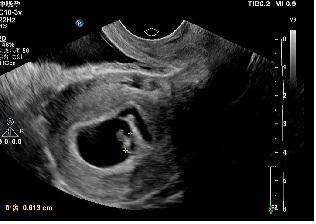

2019年10月18日一超:宫腔内见胚囊,大小17*21*22mm,胚芽长6mm,胎心136次/分。血β-HCG 56778.4、孕酮27.35、雌二醇 373.12。

一超